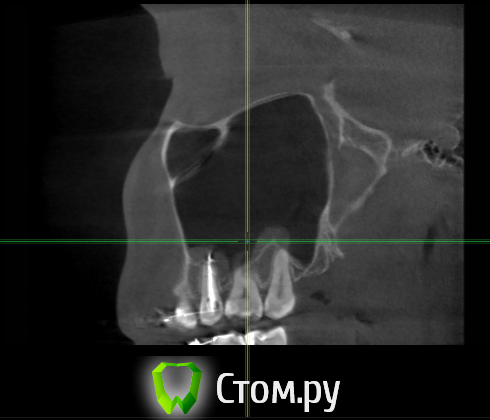

Force Опубликовано 6 апреля, 2014 Поделиться Опубликовано 6 апреля, 2014 пародонт, корни и гайморову пазуху Ссылка на комментарий

enka Опубликовано 16 апреля, 2014 Автор Поделиться Опубликовано 16 апреля, 2014 Уважаемые, ДОКТОРА! Что Вы видите на КТ? Подскажите...... Ссылка на комментарий